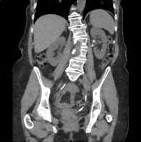

従来法

逐次近似法